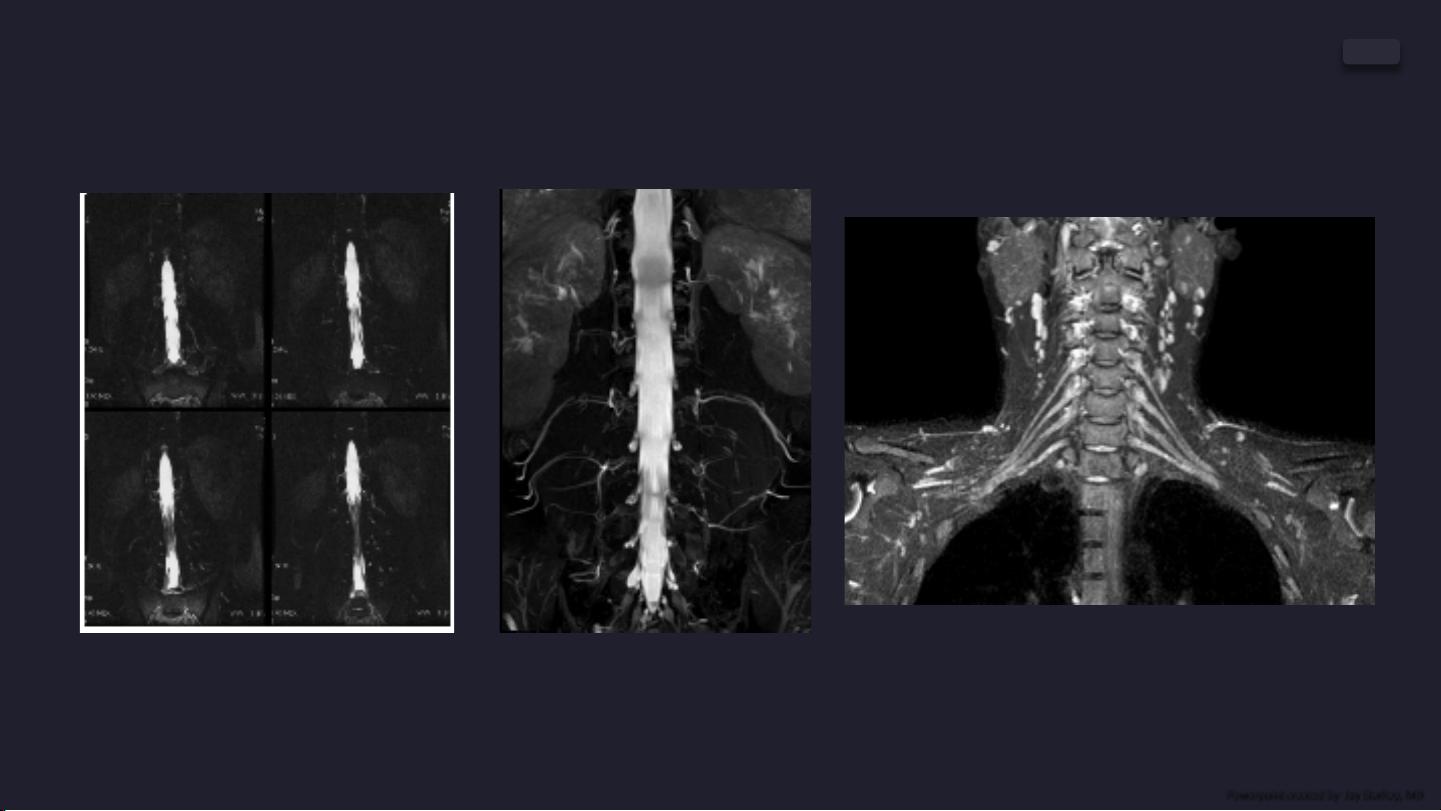

TE chụp bó rễ thần kinh đuôi ngựa

là 203 ms trên máy MRI 1.5T GE.[2]

Hình ảnh MRCP trên máy

MRI Hitachi ECHELON 1.5T

TE cho chuỗi xung STIR chụp Bó sợ thần kinh cánh tay

là 194 ms trên máy MRI 1.5T Phillips. [3]

[2] Tomoda và cộng sự (2007)

[3]Nhóm Tác giả Leong và Y.Ting (2018